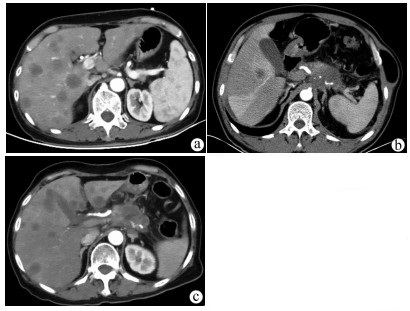

Comorbidity of hepatic cystic echinococcosis with HBV/HCV infection, liver cirrhosis, and hepatocellular carcinoma

Yang MAN, Zhiyi LIN, Zhang MIAO, Lerong YAN, Xiao CHENG, Renyi JING, Rong BAI, Pingwen HUANG, Hongwei ZHANG, Xinyu PENG

2022, 38(3): 601-605. DOI: 10.3969/j.issn.1001-5256.2022.03.020

Abstract(1231) HTML (314) PDF (2056KB)(63)

Abstract:

Objective  To investigate the comorbidity of hepatic cystic echinococcosis with HBV/HCV infection, liver cirrhosis, and hepatocellular carcinoma, and to lay a foundation for further research on the influence of hepatic cystic echinococcosis on HBV/HCV infection, liver cirrhosis, and hepatocellular carcinoma.  Methods  A retrospective analysis was performed for the data of 401 patients with hepatic cystic echinococcosis who were admitted to The First Affiliated Hospital of Shihezi University from 2003 to 2019, and the state of comorbidity of hepatic cystic echinococcosis with HBV/HCV infection, liver cirrhosis, and hepatocellular carcinoma was clarified. The patients with hepatic cystic echinococcosis and chronic HBV/HCV infection were selected as comorbidity group, and the patients with HBV/HCV infection alone were matched as control group. The chi-square test and the Fisher's exact test were used to analyze the state of viral infection and the disease composition of liver cirrhosis and hepatocellular carcinoma.  Results  Of all 401 patients, 38(9.5%) were included in the comorbidity group and 2(0.5%) had liver cirrhosis after HBV/HCV infection, while no patient had hepatocellular carcinoma after HBV/HCV infection. Among the patients with chronic hepatitis B virus infection in the comorbidity group, non-active HBsAg carriers accounted for 81%, HBeAg-positive chronic hepatitis B patients accounted for 9.5%, and HBeAg-negative chronic hepatitis B patients accounted for 9.5%; among the patients with hepatitis B virus infection in the control group, non-active HBsAg carriers accounted for 43%, HBeAg-positive chronic hepatitis B patients accounted for 33%, and HBeAg-negative chronic hepatitis B patients accounted for 19%, with a significant difference between the two groups (P=0.033). There was a significant difference in the HBV RNA clearance rate of the patients with HCV infection between the comorbidity group and the control group (χ2=4.447, P=0.035). In the comorbidity group, the patients with liver cirrhosis accounted for 5.2% and there were no patients with hepatocellular carcinoma, while in the control group, the patients with liver cirrhosis accounted for 18.4% and those with hepatocellular carcinoma accounted for 5.2%; the comorbidity group had significantly lower proportions than the control group (P=0.048).  Conclusion  The proportion of liver cirrhosis patients with hepatic cystic echinococcosis and HBV/HCV infection is lower than that of liver cirrhosis patients with viral hepatitis alone, and there are no cases of hepatocellular carcinoma after HBV/HCV infection. Further multicenter studies are needed to investigate the influence of hepatic cystic echinococcosis on chronic HBV/HCV infection, liver cirrhosis, and hepatocellular carcinoma.